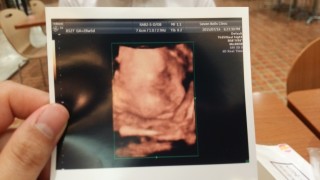

初めて3Dエコーを撮ってもらいました。 赤ちゃんの顔が見れて嬉しかったですが、少し目が離れてる気がします^_^; でも自分の子供なのでやっぱり可愛いです! 早く会えるのを楽しみにしてます!